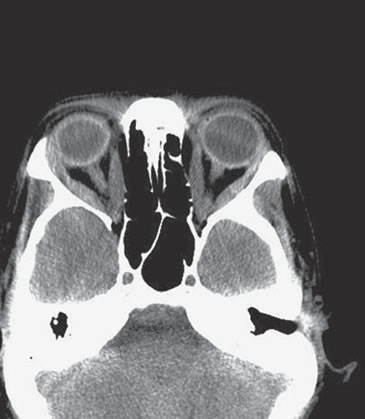

Se realizó TAC de órbitas que sólo mostró mínimo engrosamiento (bilateral) de los rectos mediales e inferiores, sin infiltración del cono posterior ni alargamiento del nervio óptico u otras imágenes patológicas (Figura 1). La campimetría computada fue normal para ambos ojos.

Figura 1. TAC de órbitas previo a tratamiento.